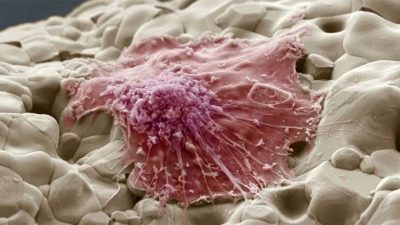

A mell patológia jelenhet formájában tömítések és előrejelzések, amelyek úgynevezett kúp. Általában, ilyen a fejlődés egy tumor. Fejleszteni dudorok a mellkas a nők és férfiak kialakulhat körül azonos valószínűséggel.

daganatok fajok

Neoplazmái, a mell tűnhet kapcsolatban a növekedés a csontszövet, amely által okozott felhalmozódása egy bizonyos részben a csont sejtek:

különböző tumor

Most tekintsük kiviteli alakoknál a jóindulatú daganatok, hogy megfigyelhető a mellkasban.